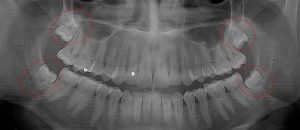

This 19 year old patient has all four 3rd molars present (circled). Only the upper left 3rd molar has fully erupted. The lower left 3rd molar is partially exposed and decaying while the lower right soft tissue impacted, both requiring extraction. Note the double crown on the upper right third molar.